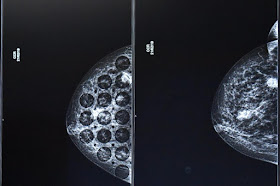

El cuerpo médico especializado en gineco-obstetricia del Hospital General de Zona 53 del Instituto Mexicano del Seguro Social (IMSS) del Estado de México Oriente, ha atendido ocho casos de tumores de ovarios en un año; en las dos últimas intervenciones, realizadas en lo que va de 2019, los cirujanos extrajeron dos tumores gigantes que sobrepasaron los 4 y 5 kilogramos.

La doctora Sandra Elena Betancourt Navarro, gineco-obstetra responsable de una reciente cirugía de extracción del tumor gigante de ovario de 5 kilos que se desarrolló en el organismo de la señora Araceli Villegas Castruita de 61 años de edad, manifestó que “los tumores pueden llegar a crecer tanto, porque éstos tiene células llamadas totipotenciales que pueden dar paso a diferentes tumoraciones”.

-Porque somos lo que comemos y desafortunadamente hoy en día muchos de los alimentos contienen hormonas y eso estimula sobre todo a la mujer, células germinales, es por eso que hay tantos casos de cáncer de mama o cáncer de ovario. Nadie está exento de enfermarse y hasta el mejor portado, en algún momento de la vida se va a enfermar, así es el cuerpo humano.